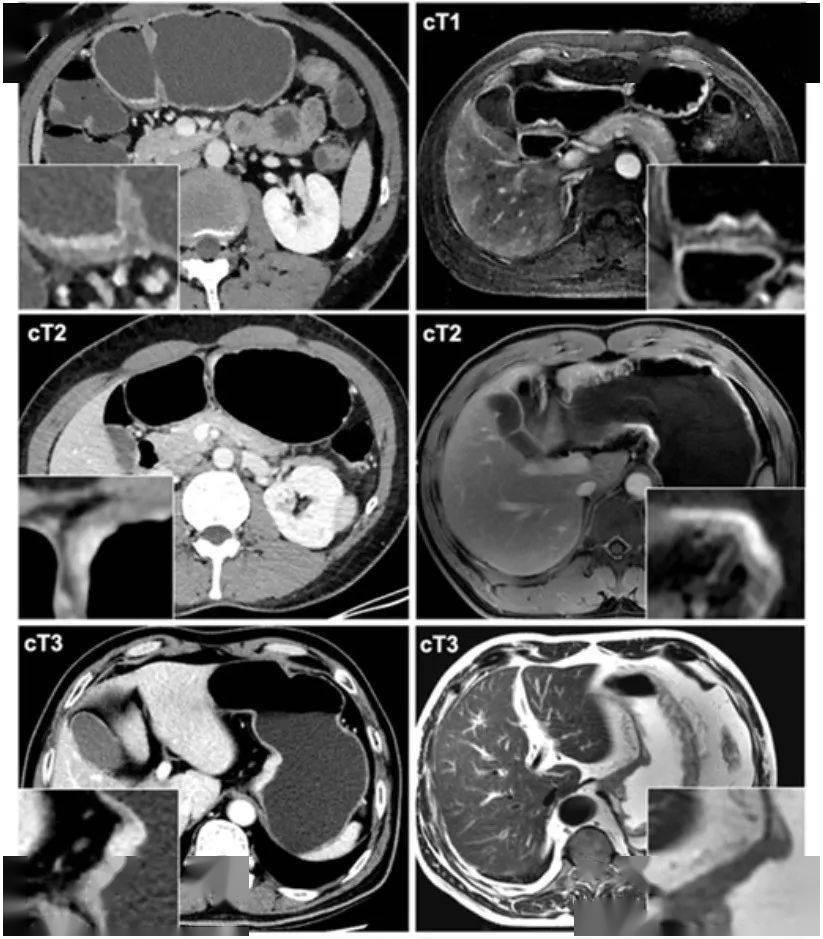

胃癌ct分期的模式图和影像图附录二:胃癌淋巴结分组no.

图片尺寸823x939